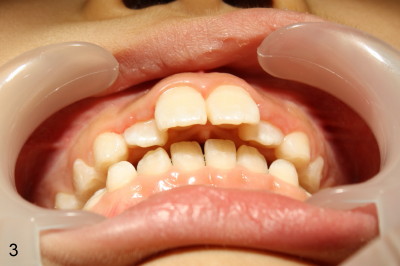

Eight-year-four-month-old boy shows early signs of Class II Division I malocclusion (Fig.2-5).  Panoramic X-ray was taken when he was 5 years 10 months old (Fig.1).

Is there any indication for phase I ortho (interceptive treatment)?  In my opinion, early orthodontics will improve appearance.  Additional Class II retraction may change canine and molar Class II occlusion into Class I so that the mandible may develop normally before permanent dentition.  If the early treatment is not done until permanent dentition as parents hope, it is most likely that orthodontics will be conducted with extraction at least two upper bicuspids.  The father has typical Class II Division I malocclusion.  What do you think?  Thanks.

2nd reply Also Xin in your case of the 8 y.o. boy, I could make the argument that the lingually positioned #7 and #10 may ultimately restrict the lower jaw from growing normally anteriorly.  Their position may very well indeed be in the way.  Check out occlusion from your pictures.  I can explain better in person perhaps.